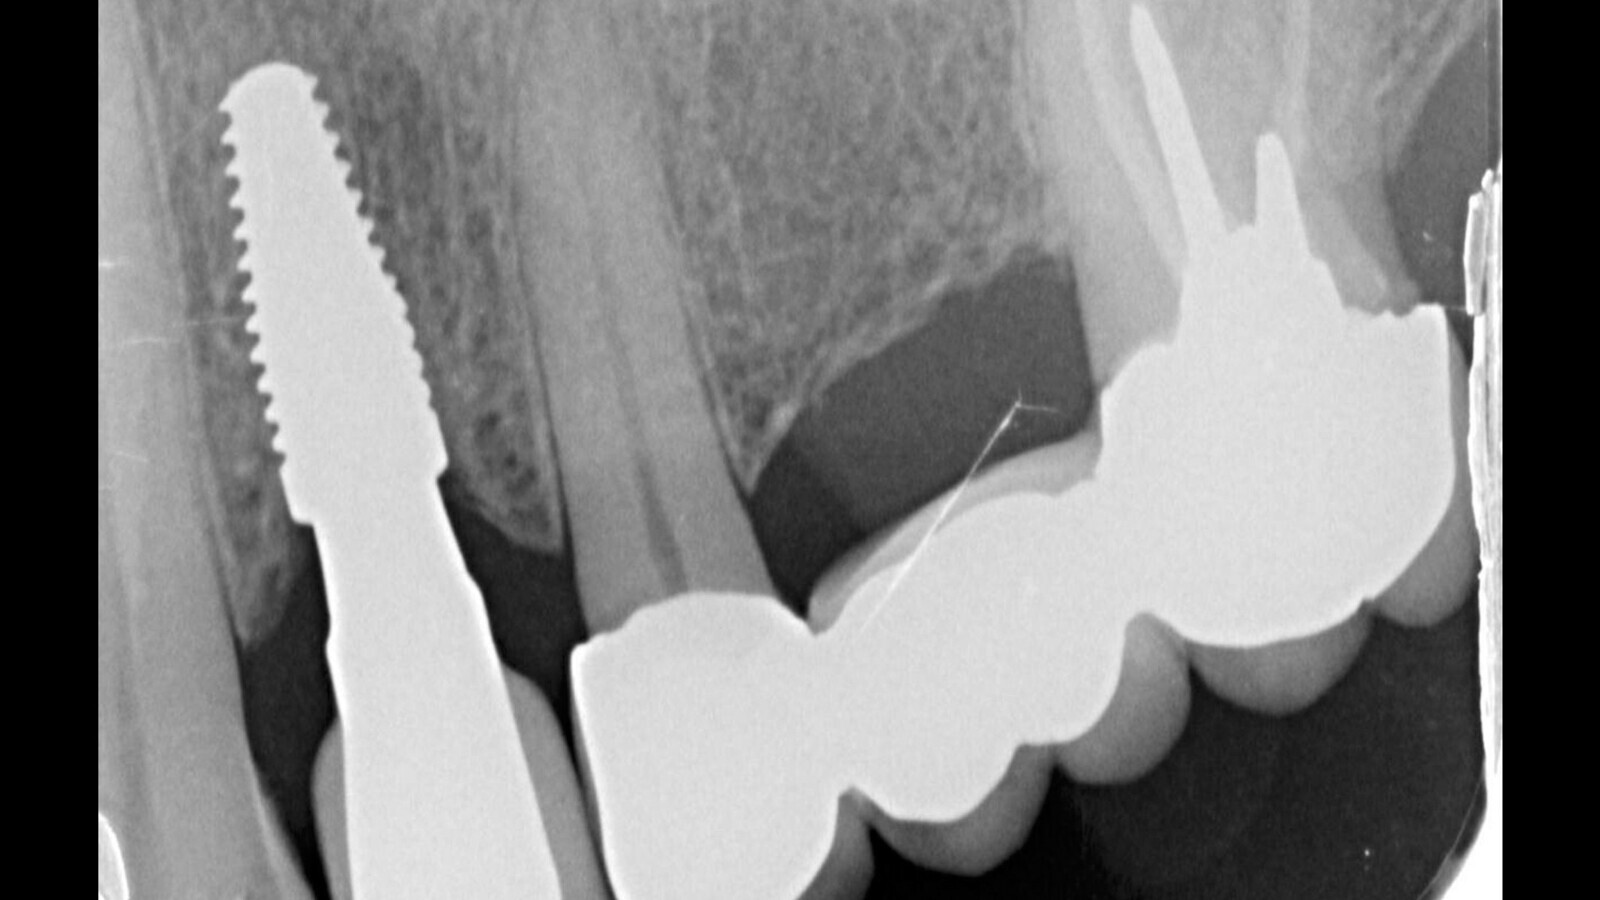

Fig. 1. Situación inicial vista por CBCT.

Tomamos una radiografía digital y una CBCT para ver si es posible hacer un implante en el área del diente 2.4.

Podemos observar un conducto radicular en el diente 27 sin lesiones apicales o intraóseas.

En el diente 24, se presenta una ausencia de anchura y altura suficiente para la implantación, sin atrofia.

Se observa una retención mucosa en el seno maxilar izquierdo.